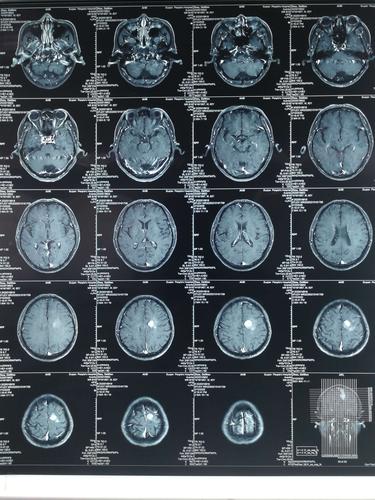

磁共振成像(MRI)是一种非侵入性的医学成像技术,通过利用磁场和无害的无线电波来生成详细的人体组织图像。MRI编程是指使用计算机编程技术来处理和分析MRI图像数据的过程。以下是关于MRI编程的一些重要信息:

MRI编程可以应用于医学诊断、研究和治疗过程中。通过编程分析MRI图像,可以帮助医生更准确地诊断疾病、评估器官功能和监测治疗效果。

在MRI编程中,常用的技术包括图像重建、图像分割、特征提取、机器学习和深度学习等。这些技术可以帮助开发人员从MRI图像中提取有用的信息,实现自动化分析和诊断。